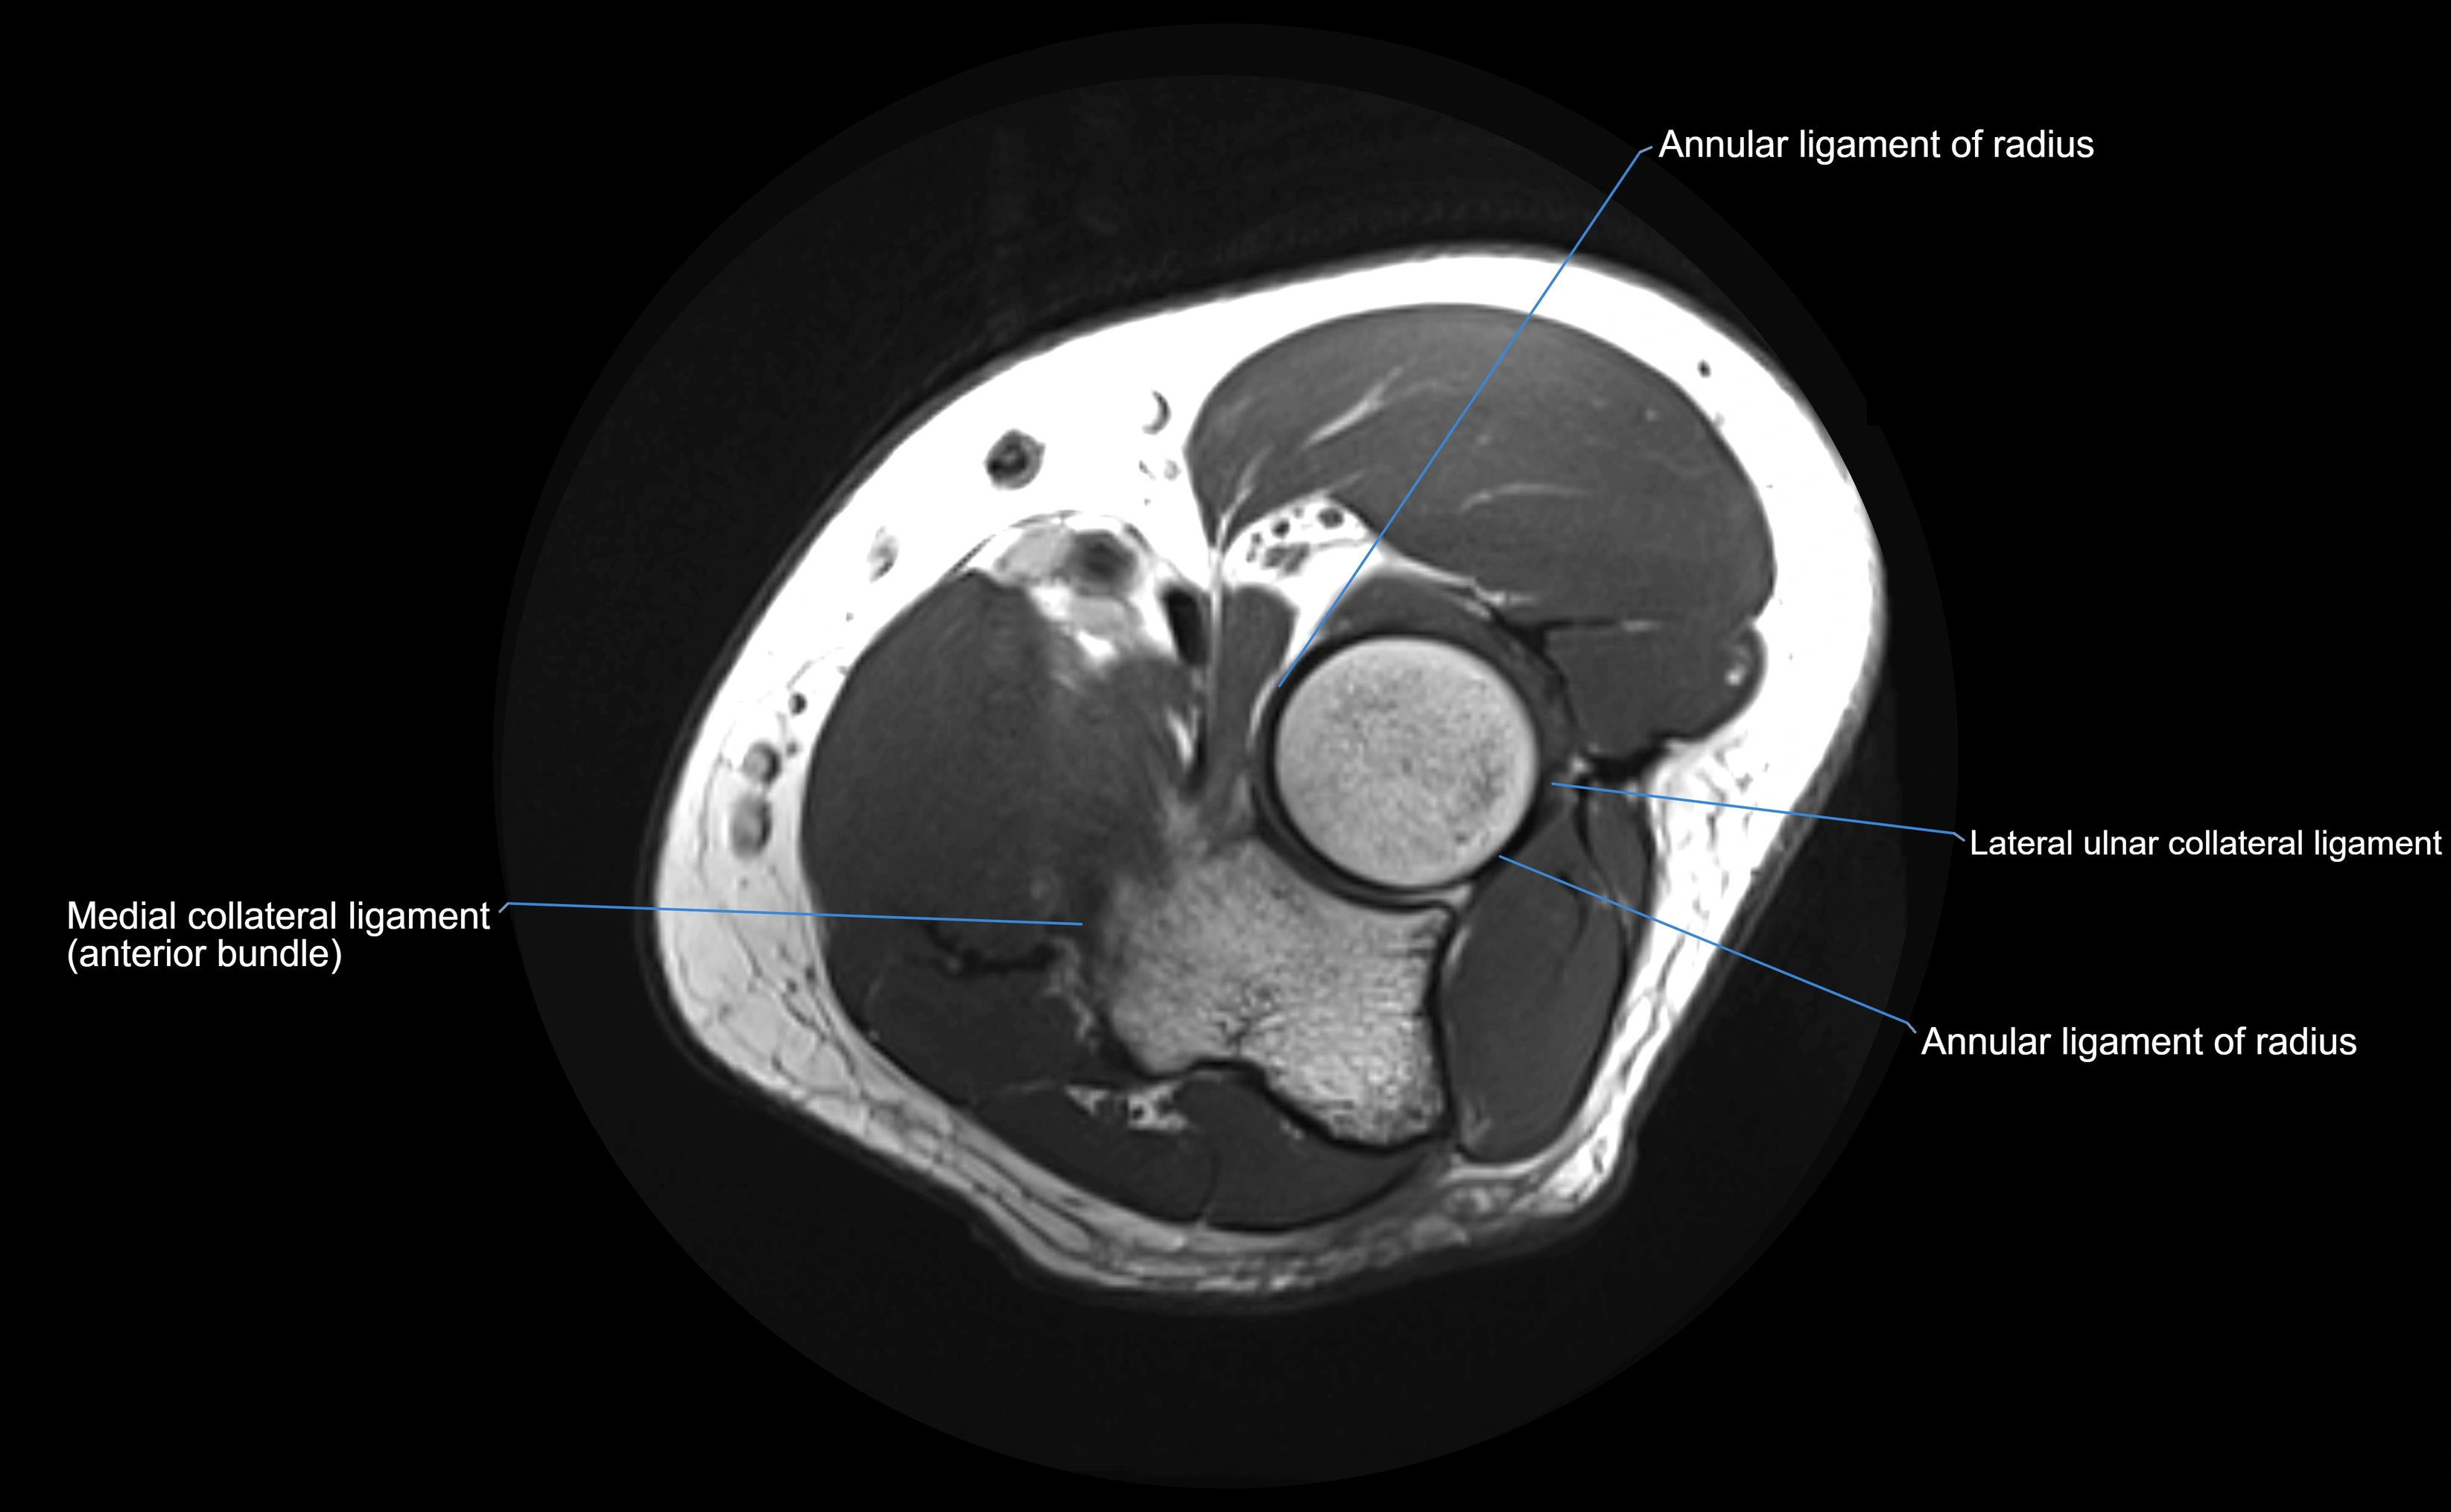

MRI Appearance

T1-weighted images:

• Ligament: low signal intensity (dark), appearing as a continuous band around the radial head.

• Adjacent fat and marrow: bright, creating contrast with the ligament.

• Thickening or disruption indicates injury or fibrosis.

• Joint capsule and synovium seen as thin low-signal lines contiguous with ligament margins.

T2-weighted images:

• Ligament: low signal (dark) with clear delineation from joint fluid.

• Fluid or edema: bright hyperintense, separating or surrounding the ligament in partial tears.

• Complete tear: discontinuity or non-visualization of ligament fibers, often with joint effusion.

Proton Density Fat-Saturated (PD FS):

• Normal: dark, well-defined band outlining the radial head.

• Partial tear: irregular or bright hyperintense signal within or adjacent to ligament fibers.

• Joint effusion and reactive synovitis appear bright and are well visualized.

MRI Arthrogram Appearance

• Contrast outlines the proximal radioulnar joint and radial head recess.

• Normal ligament appears as a dark ring surrounding the radial head, containing the injected contrast within the joint cavity.

• Partial tear: contrast extends along the ligament or beneath its fibers.

• Complete tear or subluxation: contrast extravasates around the radial head or ulna, indicating discontinuity.

• Detects capsular defects, instability, or synovial invagination with high sensitivity.

MRI images

image